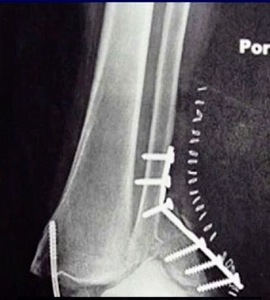

Our Randomized Controlled Trial specifically excluded those, because when I was a resident, syndesmosis injury was kept non-weight-bearing for three months, that was the standard (three months in a cast). Unfortunately, the treatment is sometimes worse than the disease. There is much controversy in terms of weight bearing for syndesmosis injuries, and not as much evidence on this specific injury compared to previously discussed ankle fractures. Figure 7 is a type of fracture we’re referring to: After you fix it, what do you do next?